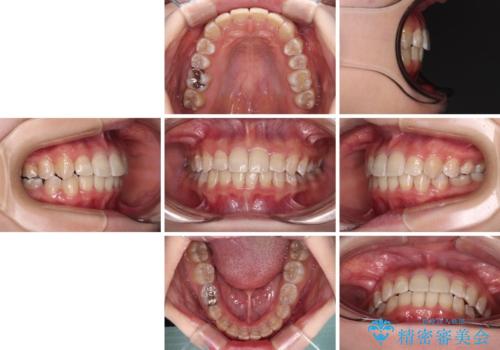

楽してクロスバイトを治したい ワイヤー装置による矯正治療

- 犬歯のクロスバイトを気にして来院された患者様です。

マウスピース矯正とワイヤー矯正の両方を提案しましたが、インビザラインの自己管理が煩わしいとのことで、ワイヤー装置による矯正治療を行うこととしました。

犬歯は歯根が太くて長いため、クロスバイトを改善するのは大変であることが多いですが、比較的スムーズに改善することができました。

インビザラインであったら、もっと期間はかかっていたような印象です。